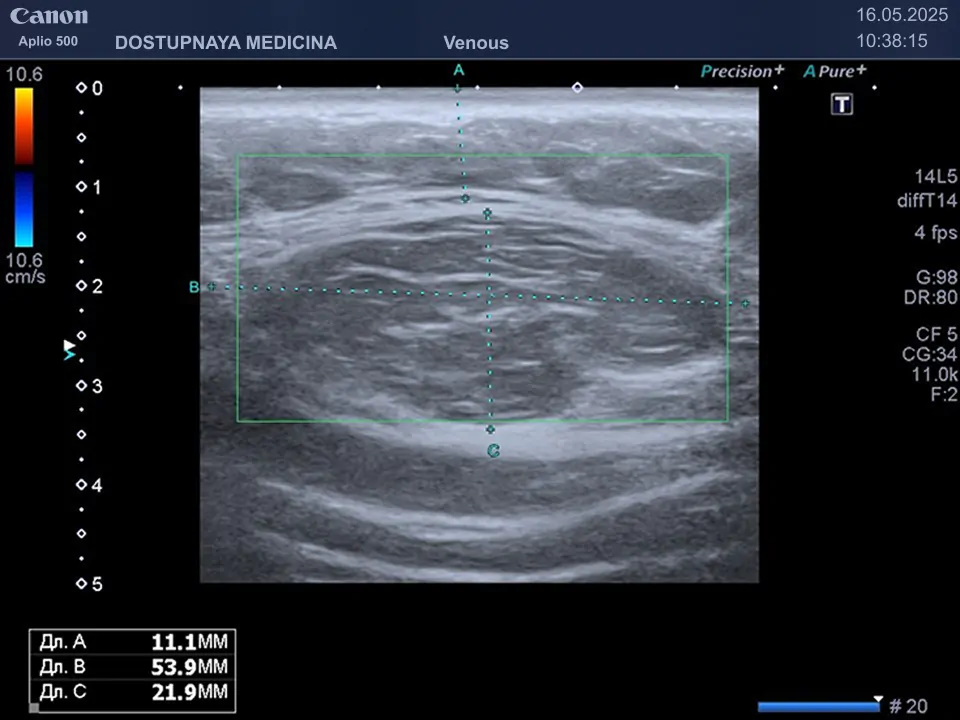

Клинический пример №3: Липома в верхней трети бедра рядом с большой                                                                                   подкожной веной бедра